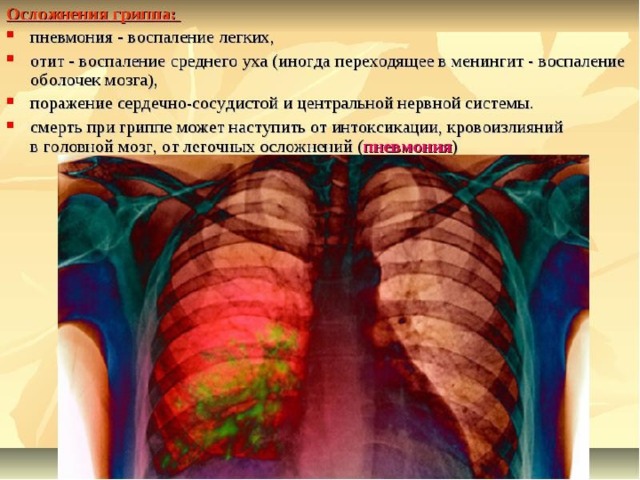

Медицинская тема: легочные осложнения при пневмонии